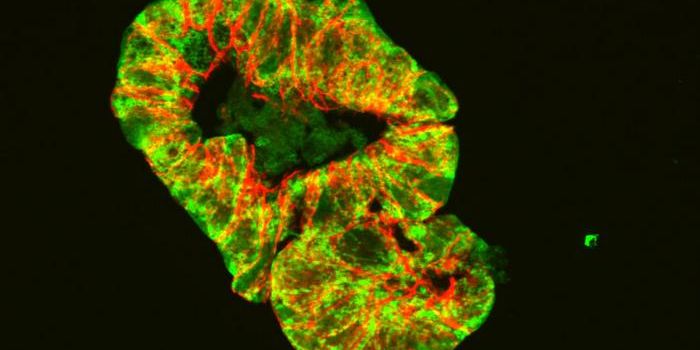

MAY 17, 2022CancerMuch has been written about scaling up cell culture for bioprocessing and other applications that require a very high de ...